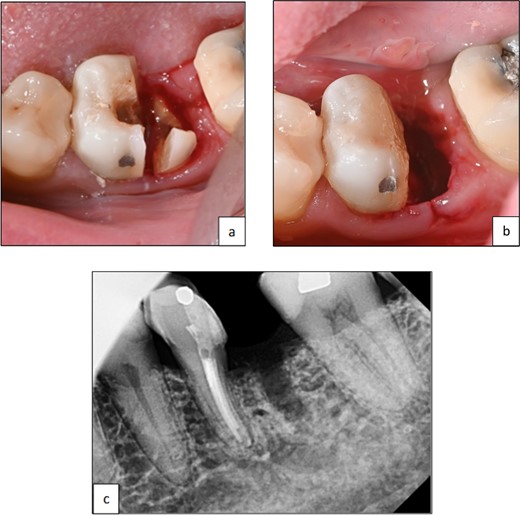

A 44-year-old patient presented to our clinic with the primary complaint of food lodgment in a cavity on the lower left posterior teeth. Clinical examination revealed extensive caries on the disto-occlusal surface of the lower left first permanent molar (tooth 36) (Fig. 1). Radiographic examination showed a large radiolucency at the distal crown extending to the cervical third of the distal root, with periapical radiolucencies on both mesial and distal roots (Fig. 2). The tooth was diagnosed with asymptomatic irreversible pulpitis and symptomatic apical periodontitis.

Clinical photograph of tooth 36 showing extensive caries on disto-occlusal surface.

Periapical radiograph of tooth 36 showing a large radiolucency area at the distal crown involving the cervical third of the distal root.